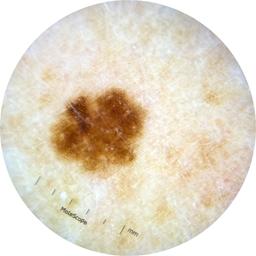

ISIC_5202282

IP_6423627

IL_0565396

Clinical

Field Value

acquisition_day 48

age_approx 50

anatom_site_1 Upper extremity

anatom_site_general upper extremity

diagnosis_1 Benign

diagnosis_confirm_type single image expert consensus

image_type dermoscopic